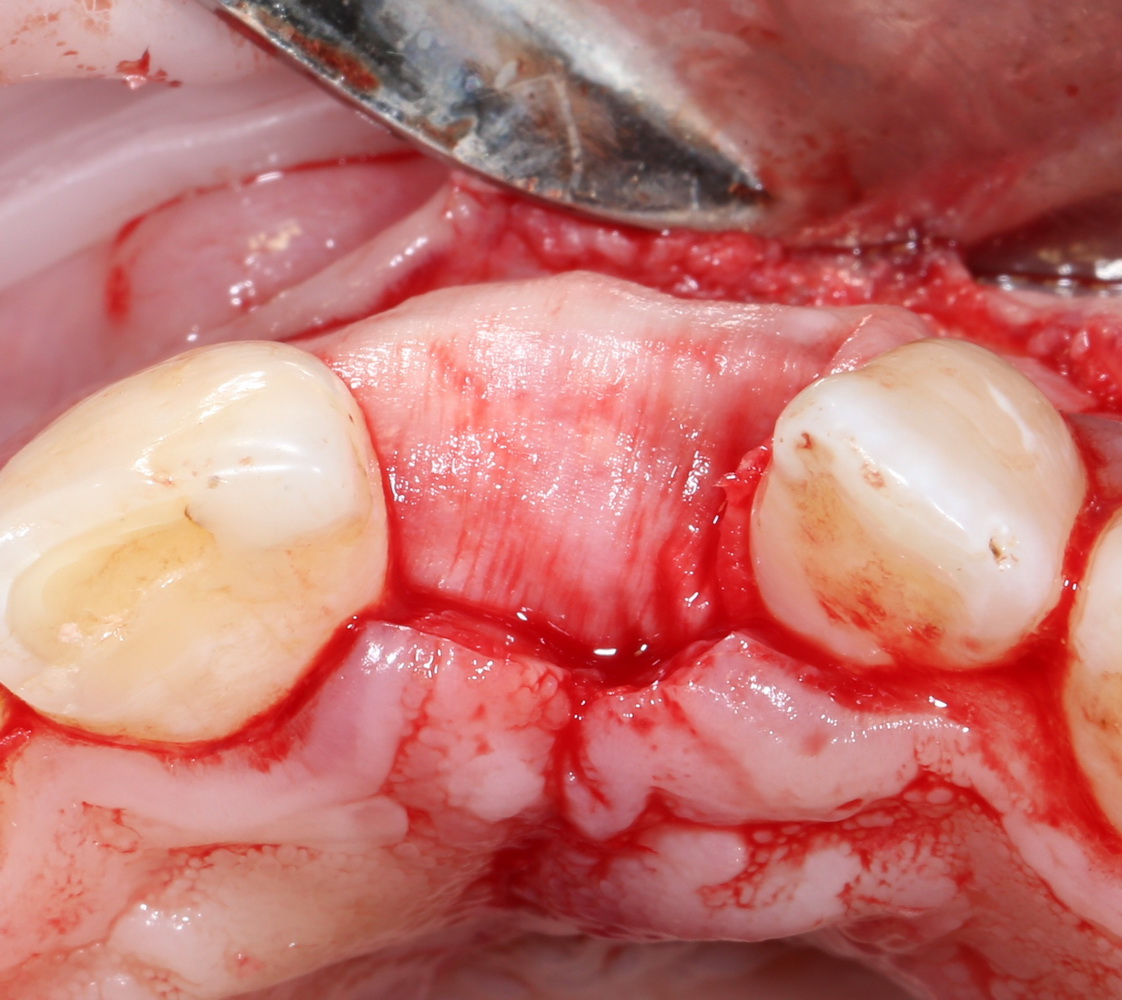

В отличие от костных блоков, делать забор аутокостной стружки можно в любом месте челюсти. Например, отдельным доступом через минимальный разрез:

или, непосредственно, со скелетированного участка операционной раны. Можно даже доступ для синуслифтинга сделать с помощью остеохарвестера, а заодно — собрать аутокостную стружку: